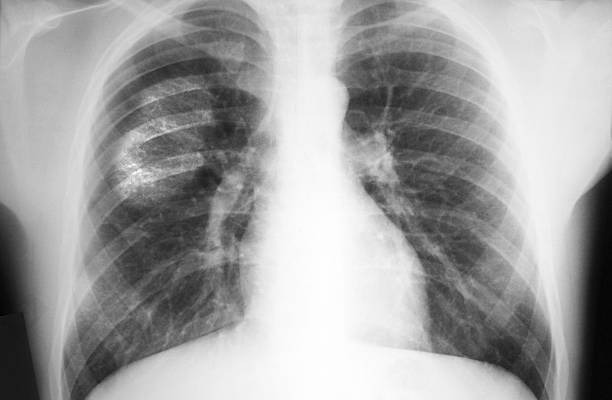

Diagnosis of ILD requires a careful and thorough evaluation by a pulmonary specialist. A detailed medical history is essential, including information about occupational exposures, medication use, family history, and underlying health conditions. Imaging studies, especially high-resolution CT (computed tomography) scans, are critical for visualizing patterns of scarring or inflammation in the lungs. Pulmonary function tests are used to assess how well the lungs are working. In some cases, a lung biopsy may be necessary to obtain a sample of lung tissue for further analysis. Blood tests and bronchoscopy (a procedure that uses a camera to look inside the lungs) may also help pinpoint the specific cause. Early and accurate diagnosis is essential for guiding treatment and slowing the progression of the disease.